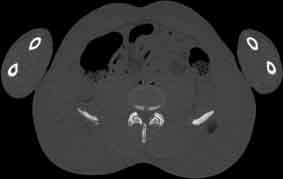

Visible Human male: Sectio transversalis 1734

CT

NMR

Pd                          / T2 \                         T1